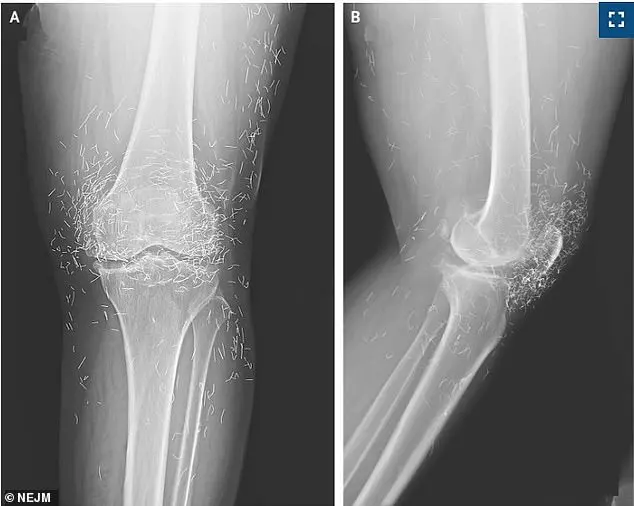

During an X-ray to assess her knee condition, doctors were stunned to discover hundreds of tiny gold threads embedded deep within her joints, a byproduct of a prior acupuncture treatment.

Min-Young Park, a radiologist at Seoul National University Hospital, who reviewed the scans. 'These threads were so numerous and diffuse that they obscured critical anatomical details, making it harder to assess the full extent of her osteoarthritis.' Osteoarthritis, a degenerative joint disease affecting over 33 million Americans and millions more worldwide, causes cartilage to erode, leading to bone-on-bone friction and chronic pain.

The X-ray revealed the threads clustered around her kneecaps, extending into her shin bone and upper thigh—a distribution that could interfere with future diagnostic imaging. 'This is a textbook example of how alternative treatments can complicate medical care,' said Dr.